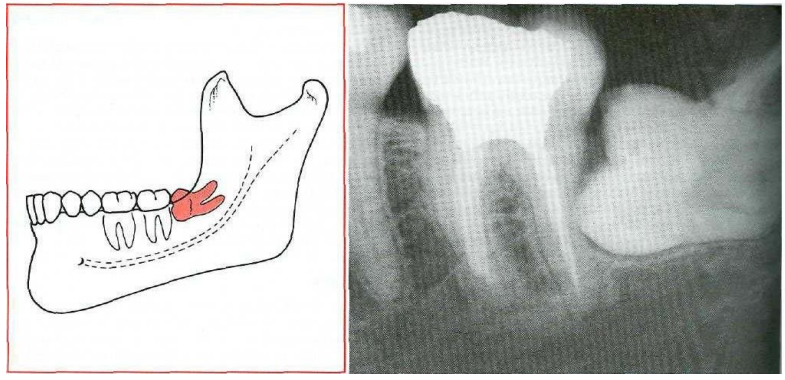

Fig-I : Mesioangular impaction. "From Contemporary Oral and Maxillofacial Surgery, chapter 9 Larry d. Peterson. Principles of management of impacted teeth p 194.

Fig .2: Distoangular impaction "From Contemporary Oral and Maxillofacial Surgery, chapter 9 Larry J. Peterson. Principles of management of impacted tooth p 195 '

Fig.3: horizontal impaction ' From Contemporary Oral and Maxillofacial Surgery, chapter 9 Larry J. Peterson. Principles of management of impacted tooth p 194

Fig 4: Vertical impaction "Contemporary Oral and Maxillofacial Surgery, chapter 9.Larry J. Peterson. Principles of management of impacted tooth p 195.

Figll Demonstrating in right side an integrated pattern of classification

(Distoangular impaction according to winter and class 3 position B according to Bell and Gregorys classification)

Impactions seen in fig. 11 are a good example of integrated pattern, reporting the type of impaction with this pattern give good estimation to the operator warn against complications like jaw bone fracture due to mass bone removal in all direction. This will help the operator to have preparedness for such mishaps and, warn the patient and get his consent for such an expected complication